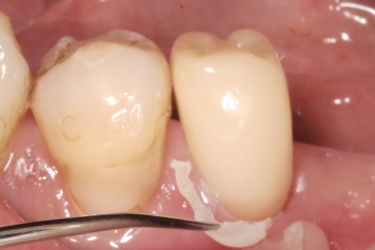

流動性の低いEXティースカラーは単冠やインレー(アンレー)の装着に、流動性の高い混和ティースカラーはポストコアや連結冠の装着におすすめです。被膜厚さはどちらも約20〜30µmです。